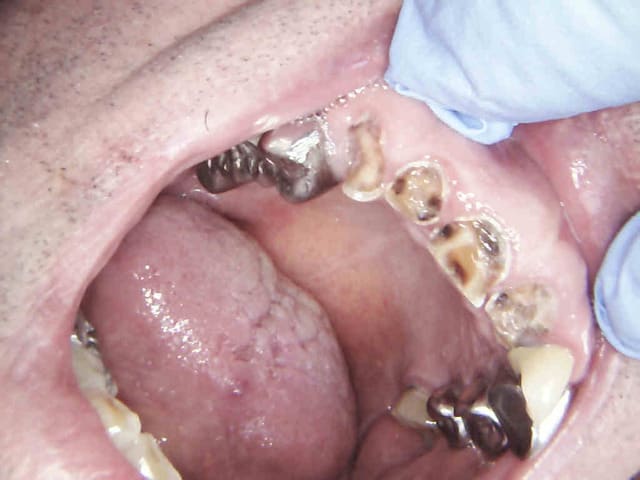

Sur une dent dévitalisée en général on couronne. Tu dois confondre a symptomatique et intactes. Elles sont intactes les dents de mon post ?

Exemple patient de 67 ans agriculteur à la retraite, revenus du couple 1200 euros par mois, cotisation mutuelle 1500 euros par an, remboursement par ceram 150 euros. Tu m'étonnes qu'il ait attendu pour aller chez le dentiste. Dents a symptomatiques (si si si) meme pas de pèches à la radio. Je dévitalise à des fins prothétiques ou je lui fout un coup de pompe dans le derche avec un devis full ceram hors de sa portée, parce que j'ai pas envie de m'emmerder avec un étalement de paiement sur les 600 euros qu'il va lui rester à charge meme au tarif CMU ? ?